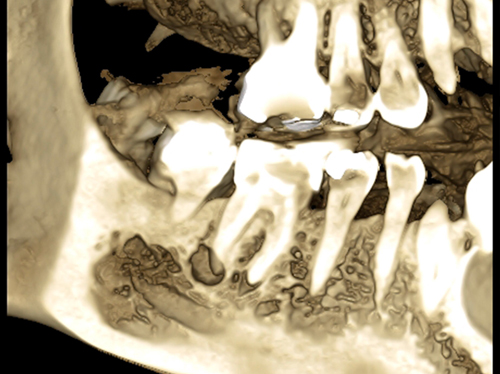

Nuestro paciente Eduardo Vicente Pedrós ha tenido en varias ocasiones infecciones en dientes que estaban desvitalizado. Él nos explica perfectamente en el vídeo que la cirugía periapical (o apicectomía) es un tratamiento que permite salvar la mayoría de los dientes afectados de esta patología.

Es una intervención técnicamente exigente, que requiere formación e instrumentos especializados (microscopio, endoscopio, etc.), pero que correctamente realizada no causa molestias prácticamente y tiene unos resultados exitosos en más del 90% de los casos.